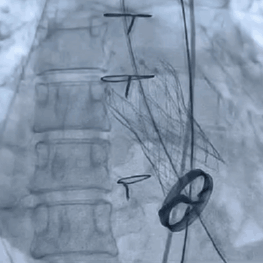

3. 术中实行的20球囊的预扩,AV26瓣膜的释放,瓣膜释放后发现还有展开的余地,故进一步选择23的球囊进行后扩使人工瓣膜更贴合主动脉根部结构。

4. 根据术前CT评估,跨瓣角度为LAO 12° CAU 5°(右窦中心位)左右,球囊预扩角度为LAO 32° CRA 2°(左冠切线位)左右,释放角度为RAO 16° CAU 24°(左右重合)左右。使用20mm球囊预扩,根据沛嘉TaurusOne®产品设计特点采取瓣环平面下2-4mm高度释放策略。

23mm球囊后扩张

瓣膜释放后造影评估

术后压差从46mmHg降至6mmHg

术后超声心动图提示:主动脉瓣人工瓣膜前向1.9m/s,平均垮瓣压差约6mmHg,微量反流,左室壁博幅正常范围,心包未见积液,手术效果良好。